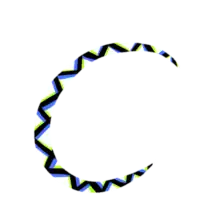

| Example of a scintillating scotoma, as may be caused by cortical spreading depression | |

A depiction of a scintillating scotoma that was almost spiral-shaped, with distortion of shapes but otherwise melting into the background similarly to the physiological blind spot. This depiction shows the type of patterning that some have described as similar to Widmanstätten patterns. A depiction of a scintillating scotoma that was almost spiral-shaped, with distortion of shapes but otherwise melting into the background similarly to the physiological blind spot

A depiction of a scintillating scotoma that was almost spiral-shaped, with distortion of shapes but otherwise melting into the background similarly to the physiological blind spot